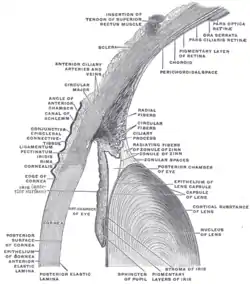

Structures of the eye labeled

Structures of the eye labeled This image shows another labeled view of the structures of the eye

This image shows another labeled view of the structures of the eye

![]() This article incorporates text in the public domain from page 1018 of the 20th edition of Gray's Anatomy (1918)

This article incorporates text in the public domain from page 1018 of the 20th edition of Gray's Anatomy (1918)